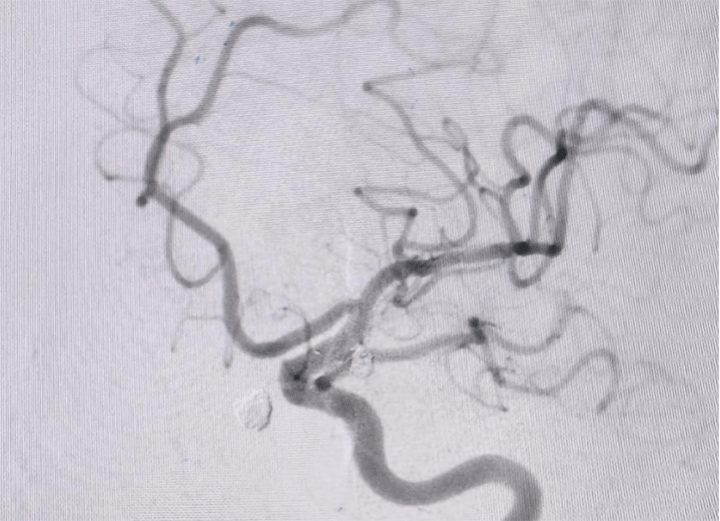

神经外科介入团队在张德辉院长的带领下,迅速启动救治方案,与患者家属充分沟通交流病情,告知患者血管条件差,手术中,医生们面临着巨大挑战,患者血管呈II型弓且迂曲严重,手术难度极高,导管到位困难,若双侧动脉瘤同时处理,手术风险极高,尽量争取一次手术解决双侧动脉瘤。

手术中造影可见右侧动脉瘤破裂小泡,为责任动脉瘤,术中予以支架辅助栓塞,考虑患者血管条件极差,若左侧同期处理,手术时间较长,容易形成血栓,增加手术风险,团队决定先处理责任动脉瘤,左侧后交通动脉瘤择期处理。

手术过程顺利,医生们凭借丰富的经验和精湛的技术,成功完成了左侧动脉瘤的处理,手术栓塞效果令人满意。由于是未破裂动脉瘤,患者恢复速度较快,术后仅3天就达到出院标准。